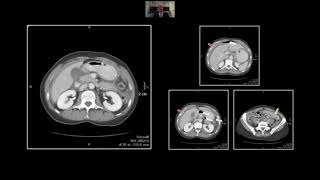

Proximal Gastrointestinal Emergencies | Interesting Radiology Cases video

Proximal Gastrointestinal Emergencies | Interesting Radiology Cases

Proximal Gastrointestinal Emergencies | Interesting Radiology Cases CT of Upper Gastrointestinal Emergencies | Free Radiology CME